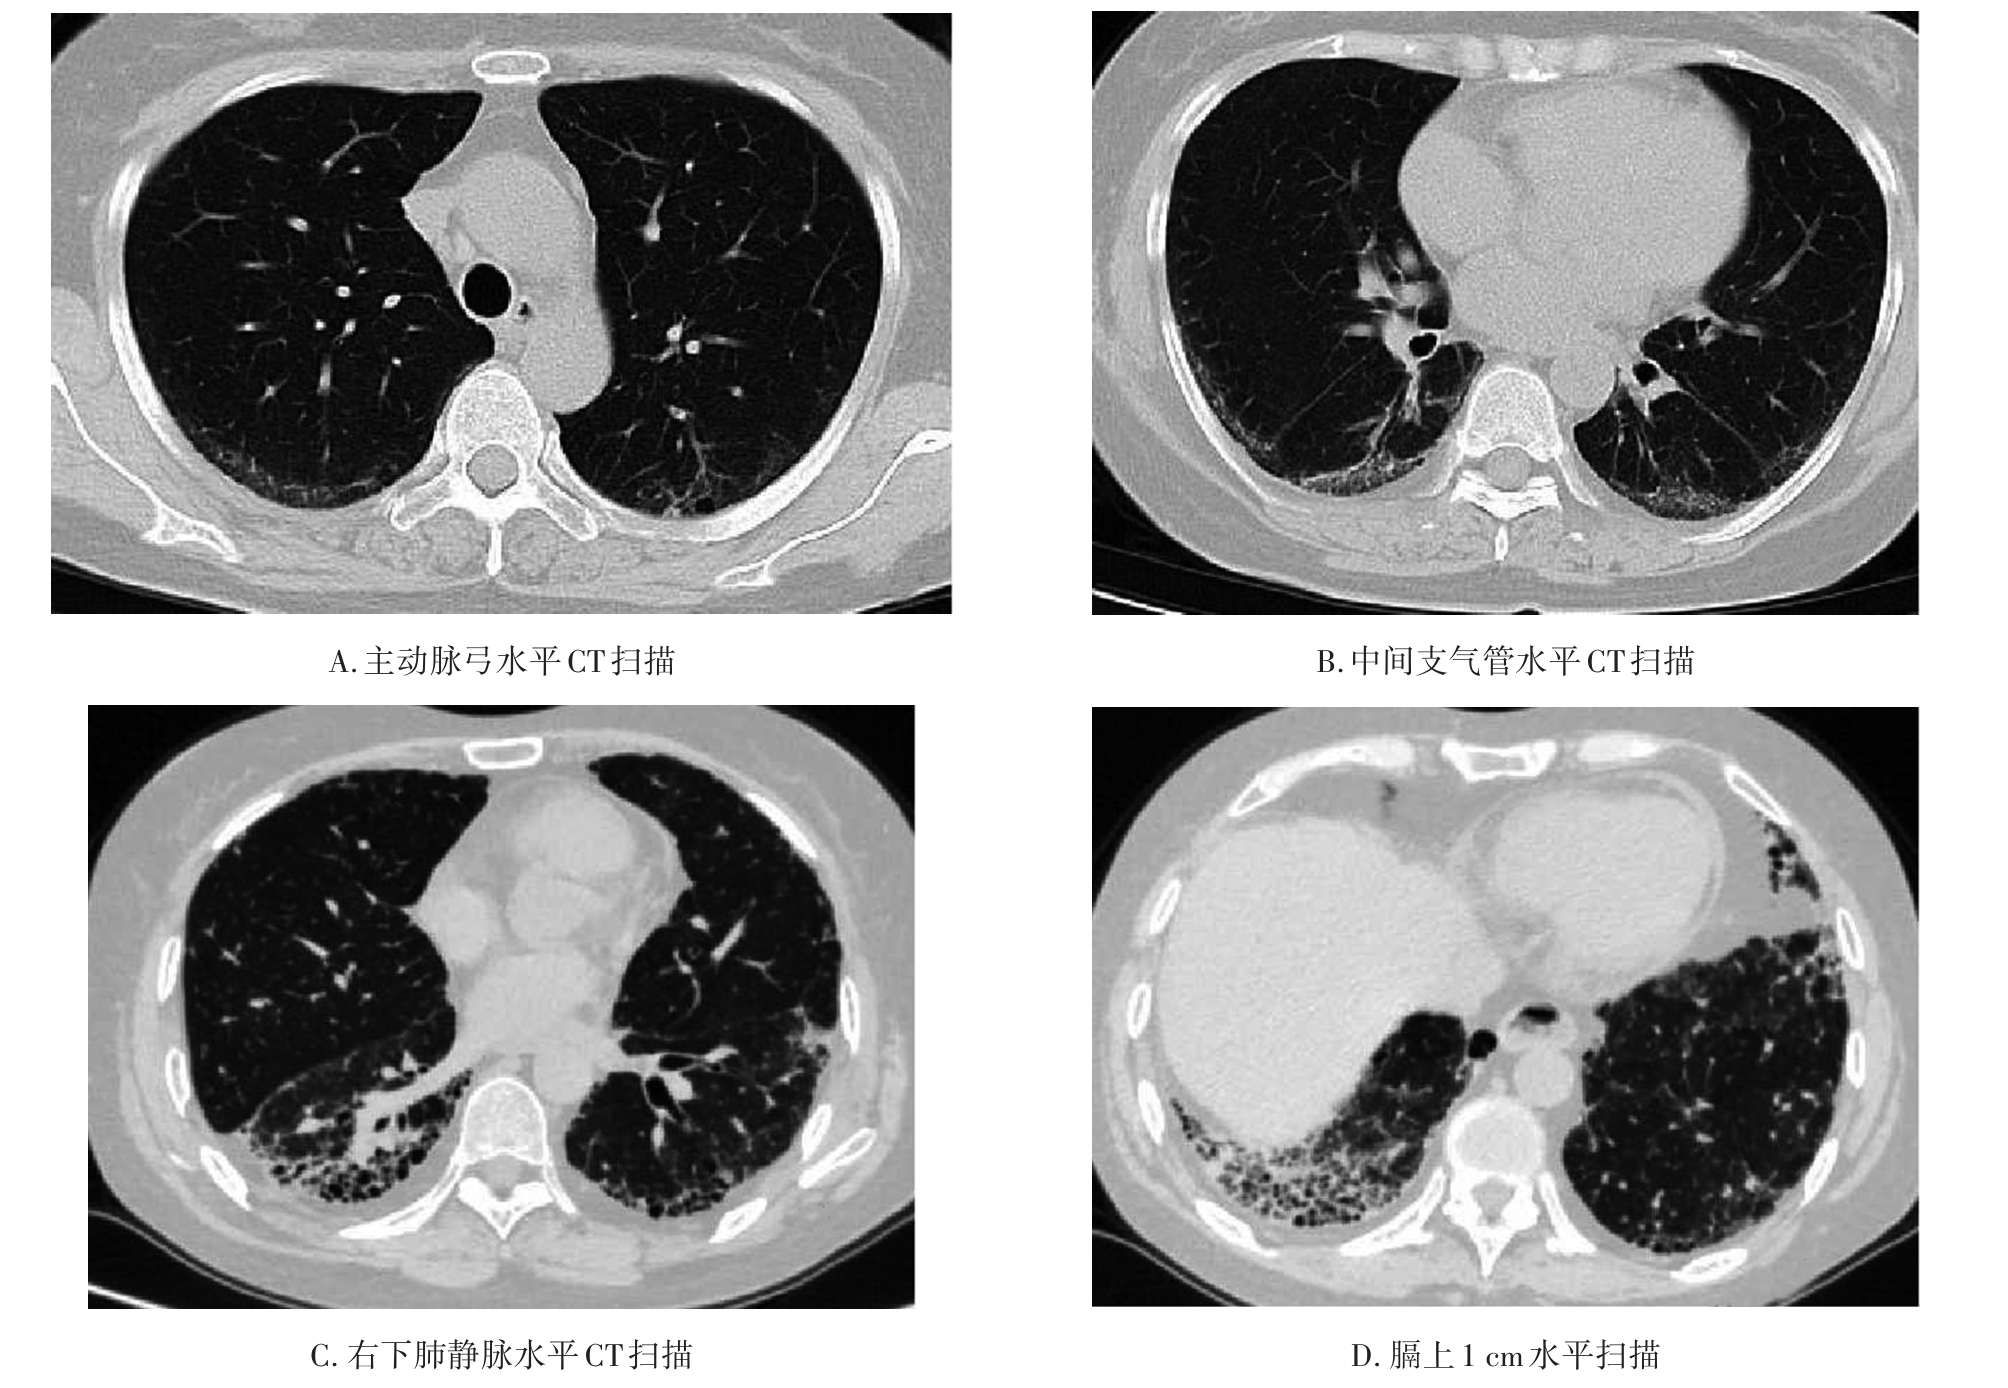

• 系统性红斑狼疮患者肺部影像学特征与疾病活动度相关性研究

2023, 48(11):1351-1355. DOI: 10.13406/j.cnki.cyxb.003353

摘要 (94) HTML (39) PDF 1.35 M (174) 评论 (0) 收藏

摘要:目的 探讨系统性红斑狼疮合并间质性肺病的CT特征与疾病活动度的相关性。方法 纳入131例系统性红斑狼疮相关间质性肺病患者。分析其疾病活动度评分、影像学特征及高分辨CT(high resolution computed tomography,HRCT)肺间质纤维化Kazerooni评分。采用Spearman秩和相关系数检验分析各评分之间的相关性。结果 Kazerooni评分法中的磨玻璃评分与系统性红斑狼疮疾病活动度-2000评分(systemic lupus erythematosus disease activity index-2000,SLEDAI-2000)呈正相关,差异有统计学意义(rs=0.388,P<0.001)。而纤维化评分与SLEDAI-2000评分之间差异无统计学意义(P=0.837)。弥漫性肺泡损伤(diffuse alveolar damage,DAD)组磨玻璃评分得分最高,寻常型间质性肺炎(usual interstitial pneumonia,UIP)组纤维化评分得分最高,差异有统计学意义(均P<0.001)。比较不同间质性肺病(interstitial lung disease,ILD)类型之间SLEDAI-2000评分差异无统计学意义(P>0.05)。结论 胸部HRCT可有助于更全面地评估系统性红斑狼疮疾病情况,对制定治疗方案具有重要意义。